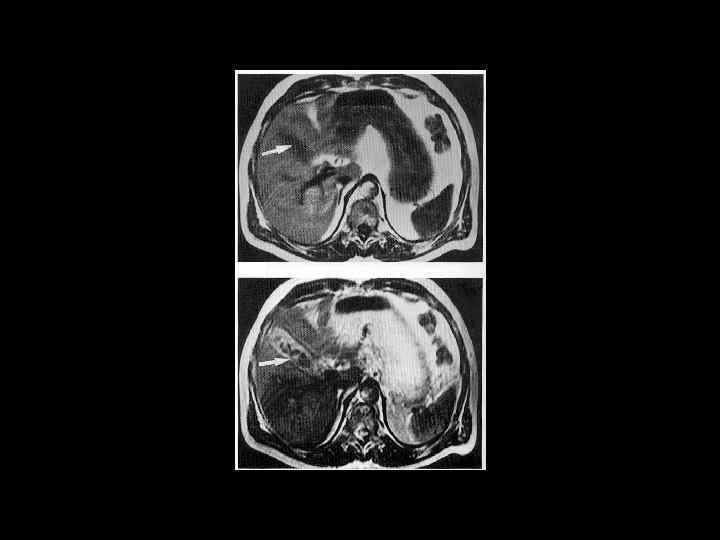

АКТУАЛЬНЫЕ ВОПРОСЫ РЕНТГЕНОЛОГИИ ЛУЧЕВАЯ ДИАГНОСТИКА ЗАБОЛЕВАНИЙ ЖЕЛЧЕВЫДЕЛИТЕЛЬНОЙ СИСТЕМЫ Желчекаменная болезнь МР семиотика